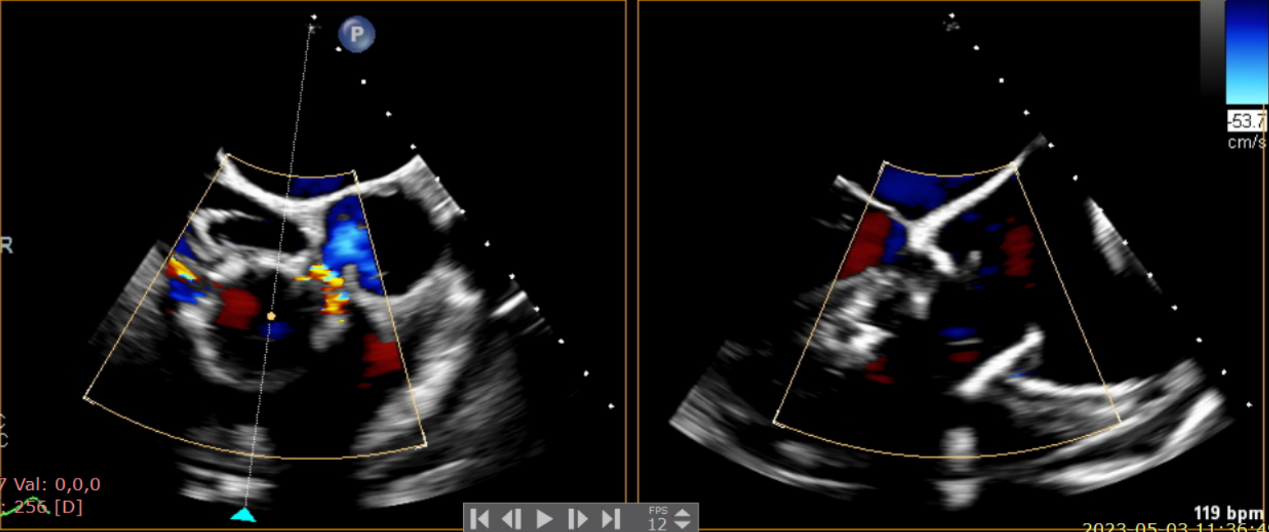

術前超聲提示大量三尖瓣反流

術中輸送器在超聲引導下調整位置

術后超聲提示無瓣周漏

術后超聲提示僅殘余輕微瓣周漏